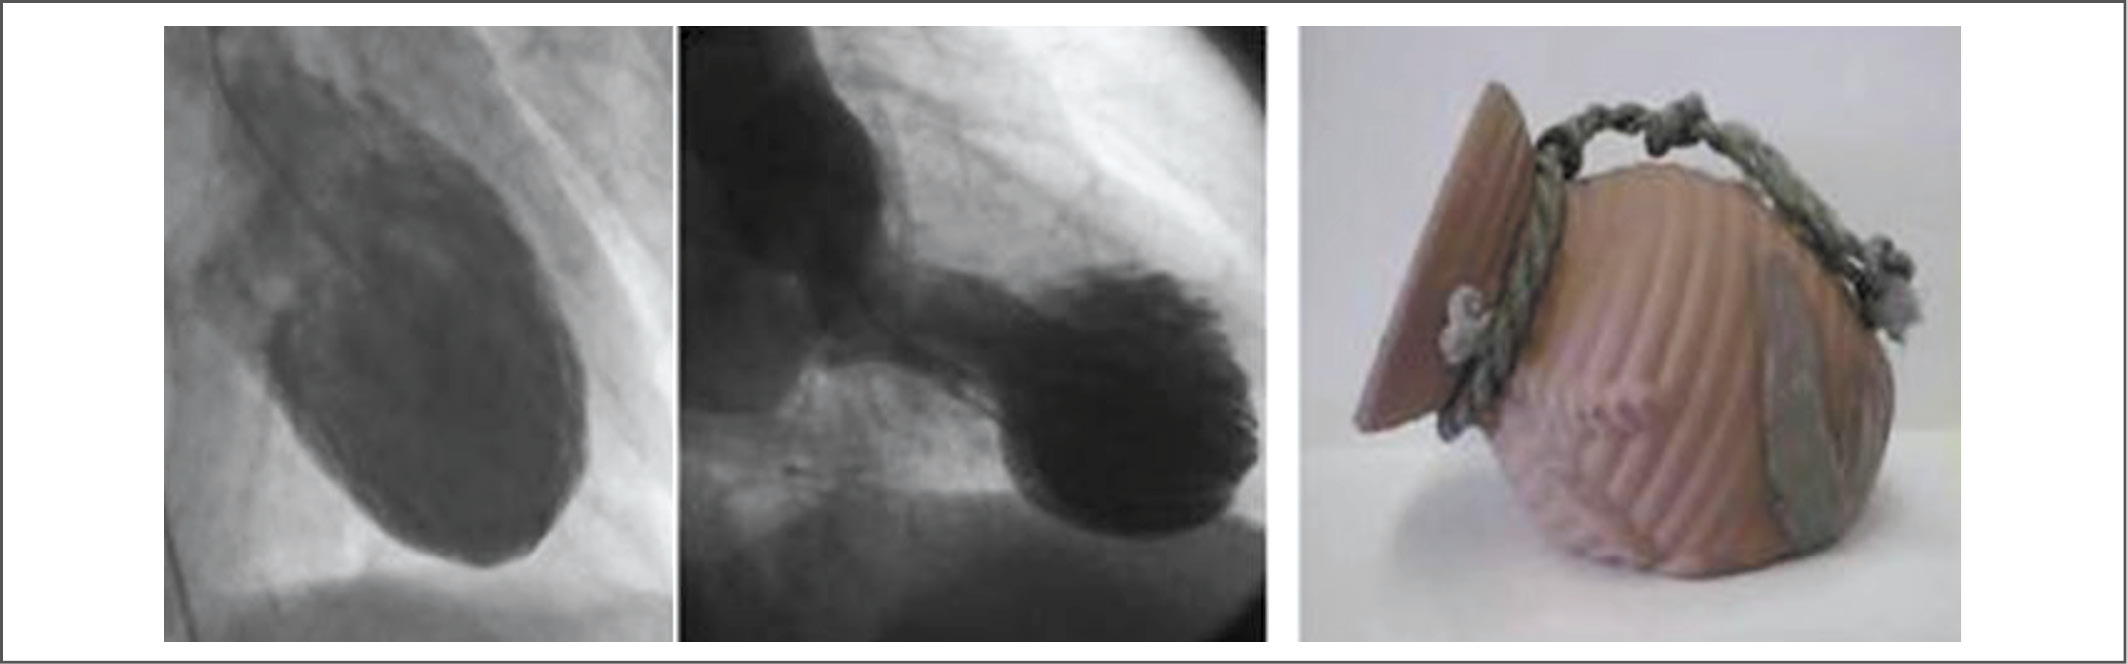

Синдром такоцубо (СТ; takotsubo-кардиомиопатия), или стресс-индуцированная кардиомиопатия, также называемая синдромом разбитого сердца, синдромом апикального баллонирования или преходящей дисфункцией левого желудочка (ЛЖ), становится всё более известным. Впервые он был описан в Японии в 1990 г. H. Sato и соавт. [1]. Термин «такоцубо» (tako-tsubo) в переводе с японского языка означает приспособление для ловли осьминогов – керамический горшок с круглым основанием и узким горлышком. Именно такую форму у больных приобретает ЛЖ в систолу, что видно при проведении эхокардиографии (ЭхоКГ) и объясняется отсутствием сокращения верхушки ЛЖ с одновременным избыточным сокращением базальных отделов (рис. 1, 2). СТ обычно характеризуется транзиторной систолической дисфункцией и обширной акинезией апикальных и/или средних сегментов ЛЖ, жалобами и изменениями при выполнении электрокардиографии (ЭКГ; рис. 3), имитирующими острый коронарный синдром (ОКС), но при отсутствии значимой обструкции коронарных артерий, а также с ограниченным выбросом сердечных маркёров [2, 3].

Рис. 1. Результаты вентрикулографии. Размеры ЛЖ в диастолу (слева). Признаки систолического (средний рис.) баллонирования верхушки ЛЖ при кардиомиопатии такоцубо. Горшок для ловли осьминога (справа).

Fig. 1. Results of ventriculography. Dimensions of left ventricle in diastol (left). Symptoms of systolic (Middle Fig.) ballooning of the top of the left ventricle in takotsubo cardiomyopathy. Octopus pot (right).

Наиболее специфичные изменения выявляются при ЭхоКГ и контрастной вентрикулографии (см. рис. 1, 2). Трансторакальную ЭхоКГ считают методом выбора для определения варианта поражения миокарда и сократительной способности ЛЖ при СТ. Характерны а- или дискинез верхушки и средней части ЛЖ с гиперконтрактильностью основания и обструкцией выходного тракта ЛЖ (taco-tsubo). Общая систолическая функция снижается, иногда значимо (до 20%).